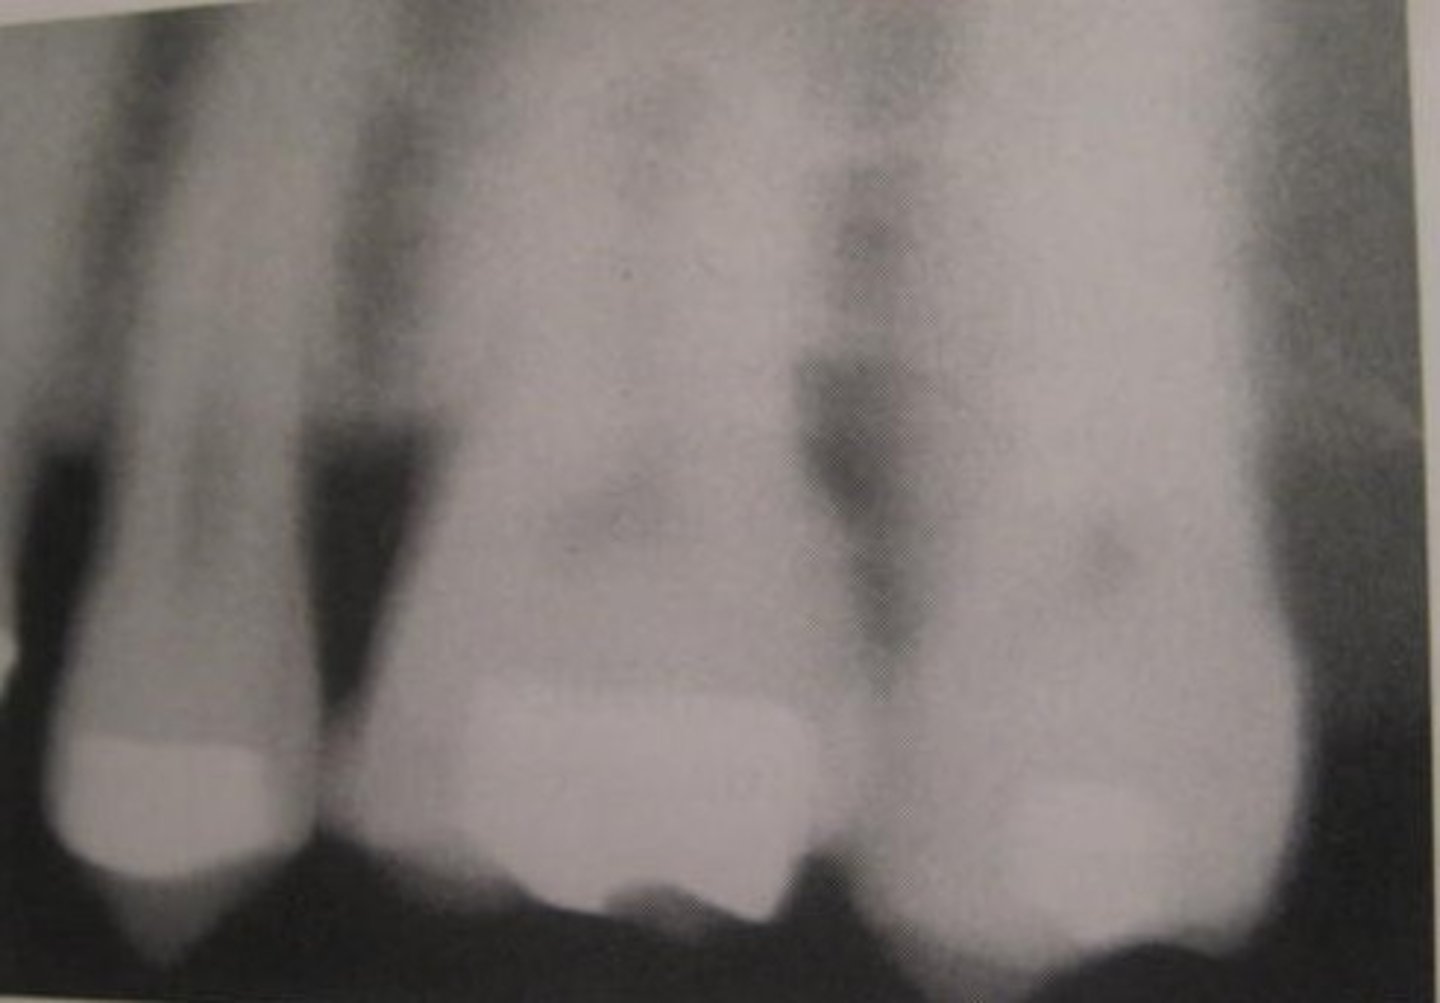

foreshortened images

teeth appear short with blunted roots

caused by too steep vertical angulation